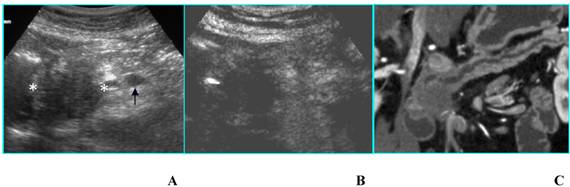

Fig 7

Double benign intraductal papillary mucinous tumor in an asymptomatic 72-year-old woman. A. B-mode US shows two simple cysts (arrows) located in the head of the pancreas. B. CEUS confirms the presence of two simple cysts without septa or mural nodules (arrows). C and D. MR on axial T2-weighted image (C) confirms the unilocular aspect of the cysts (arrows) and on coronal T2-weighted image (D) well demonstrates the communication of the greater cyst with the pancreatic duct (arrowhead).

Int J Med Sci Image

Likewise, when two or more unilocular cysts are present, the differential diagnosis – restricted between pseudocysts and IPMTs [12] - cannot be made by CEUS and the resort to CT or MR is mandatory (Fig. 7).